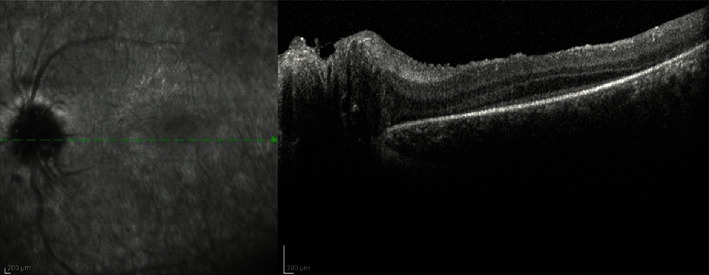

一例患者Alström综合征(AS)被误诊为Leber的遗传性视神经病变或色素性视网膜炎13年提出。AS是一种罕见的由ALMS1基因突变引起的遗传病。AS可导致纤毛的形成和功能异常。AS影响代谢,症状包括2型糖尿病(T2DM)、肥胖、男性性腺功能减退和男性乳房发育症、进行性双侧感音神经性听力丧失、心肌病、非酒精性脂肪性肝病(NAFLD)、肝硬化和慢性进行性肾病。上述症状的发作可能差别很大。眼部表现为早发性锥体杆营养不良,在出生后的头几个月开始表现为进行性视力丧失、畏光和眼球震颤。准确的诊断可以使专家在患者的日常生活中发挥显著的积极作用。遗传咨询也可以推荐给这些患者。诊断是通过DNA检测来确认的,从而突出了其在日常实践中的必要性。

A case of a patient with the Alström syndrome (AS) that was misdiagnosed as Leber's hereditary optic neuropathy or retinitis pigmentosa for 13 years is presented. AS is a rare genetic disorder caused by mutations in the ALMS1 gene. AS may lead to abnormal ciliary formation and function. AS affects metabolism, and symptomatology includes type 2 diabetes mellitus (T2DM), obesity, hypogonadism and gynecomastia in males, progressive bilateral sensorineural hearing loss, cardiomyopathy, nonalcoholic fatty liver disease (NAFLD), cirrhosis, and chronic progressive kidney disease. The onset of the above symptoms may vary significantly. The ophthalmic manifestation is early onset cone-rod dystrophy that starts as progressive vision loss, photophobia, and nystagmus in the first months of life. An accurate diagnosis may enable specialists to facilitate a significantly positive effect in the everyday life of a patient. Genetic counseling may also be recommended for these patients. Diagnosis was confirmed by DNA testing, thus highlighting its necessity in everyday practice.